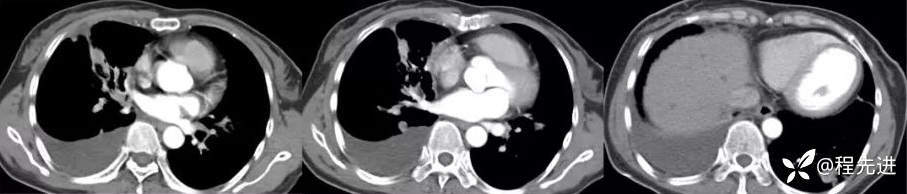

纵隔窗

增强动脉期